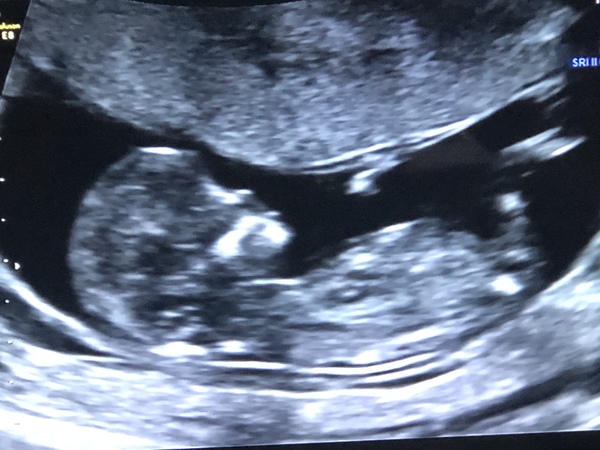

Hello everyone I am so terrible keeping up to date with this and I've been so poorly with headaches.. they make me cry they're dreadful. Seeing some lovely scan pics.. I'm terrible at guessing genders lol I seem to always get wrong lol. Had my scan today and have a healthy wriggler. Anyone fancy guessing gender 💫

@Herewego2020 what a beautiful clear scan!

I would say girl for skull theory but I am not sure about the nub. It's definitely pointing upwards but it parallel with the bottom half of the bottom so this could just be because babies bodie was tilting upwards!

I'm really starting to doubt these nub theories the more I read into them, but it's all just a bit of fun isn't it :)

@november90 thank you 😃 well you have more knowledge then me I dont know what to look for 😂 I showed my sons the picture and my oldest said "baby has a big head" 😂

@facevalue wow that picture is so clear how precious. We find out sex December but doing gender reveal which may have to happen after christmas.. the wait might do me in lol

@herewego2020 i was just going to say congrats to you too and lovely baby pic. i keep seeing girls so i'm saying girl for u too 😂 i mentioned the skull/nub theories to the sonographer and he gave me a dirty look and said ' i have no idea what u r talking about' 😳 he shut me up for sure